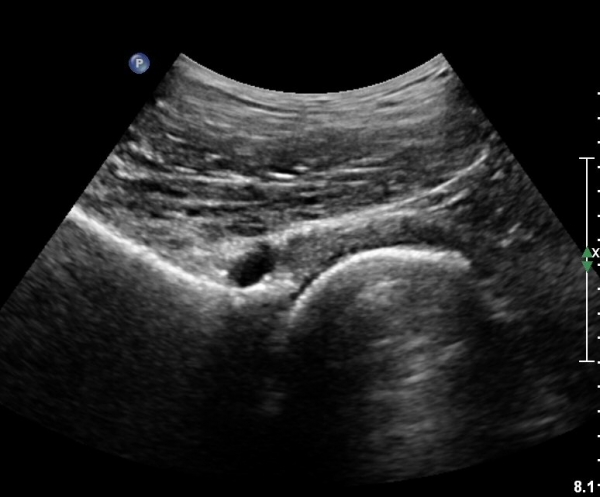

[¾ûµ¢ÀÌ] ¾ûµ¢ÀÌ °üÀý¼ø ÆÄ¿­ÀÇ ÃÊÀ½ÆÄ°Ë»ç(ultrasonography of labrum tear of hip joint)

Sonography of the Acetabular Labrum Visualization of Labral Injuries During Intra-Articular Injections

Sonographic evaluation of anterosuperior hip labral tears with magnetic resonance arthrographic and surgical correlation.